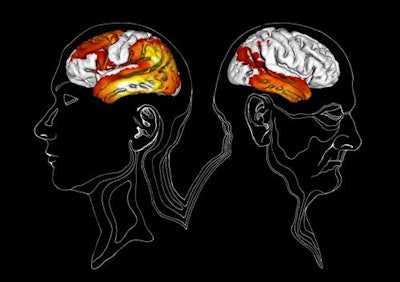

Through the AV-1451-PET images, the researchers discovered unique uptake patterns in both early- and late-onset Alzheimer's patients. In a comparison with healthy controls, the early-onset disease group showed greater uptake in most of the temporal, lateral parietal, lateral occipital, and dorsal frontal cortical regions. Uptake among the late-onset Alzheimer's patients was greatest in the medial temporal lobe.

When the researchers matched subjects with Alzheimer's, the early-onset group had significantly more uptake in the dorsolateral prefrontal, premotor cortex, and the inferior parietal lobule (p < 0.001) than the late-onset subjects.

"The changes in the various parts of the brain that we can see in the images correspond logically to the symptoms in early onset and late onset Alzheimer's patients respectively," the authors wrote. "Our findings suggest that the inferior and medial temporal cortex may be the most optimal regions of interest to yield maximum diagnostic accuracy across the wide clinical spectrum of Alzheimer's disease."